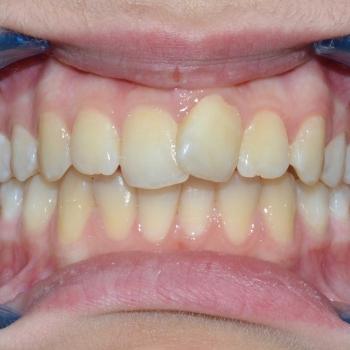

Eszter és édesanyja az iskolai fogorvosuk javaslatára kerestek fel, mert a kolléga, az esztétikai problémát okozó torlódás mellett, Angle II. osztályú funkciós eltérést is tapasztalt. Szerencsére ezeken felül egyéb eltérésre a konzultáció alkalmával sem derült fény.

Eszter a kezelés megkezdésekor headgear típusú fogszabályozó készüléket kapott annak érdekében, hogy a felső nagyőrlőket hátrafelé mozgassuk, illetve, hogy a keletkező rést felhasználjuk a kisőrlők és a szemfogak hátramozdítására is. Az így felszabadult hely az Eszter által választott hagyományos fém fogszabályozó segítségével felhasználható volt a metszőfogak elrendezéséhez, azok túlzott előredőlése nélkül.

A kezelés eredményeként minden kiindulási problémát sikerült megoldani és egy esztétikailag és funkcionálisan is szép mosolyt létrehoznunk.